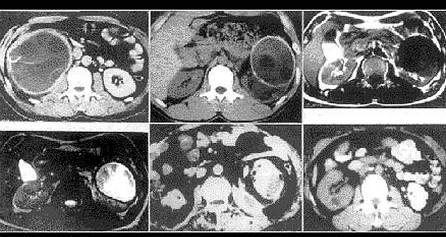

选项 A、输精管结核病变时变得粗硬并呈“串珠”样改变 B、病变主要从前列腺、精囊开始,故临床上表现最明显的是前列腺和精囊结核 C、含有结核杆菌的尿液可以进入生殖系统致病 D、男性肾结核病人中约有50%~70%合并生殖系统结核 E、男生殖系统结核也可以经血行直接播散引起